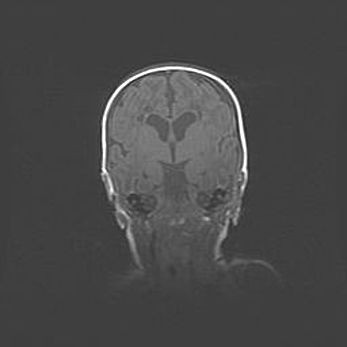

Открытая гидроцефалия.

Возраст: 9 месяцев 12 дней

Вес: 6800 г

Пол: мужской

Окружность головы: 41,5 см

Срок гестации: 28 недель

Гидроцефалия головного мозга у новорожденных имеет характерный признак: опережающий рост окружности головы приводит к визуально хорошо определяемой гидроцефальной форме сильно увеличенного в объёме черепа. Детские неврологи определяют следующие симптомы гидроцефалии у грудничков: выбухающий напряжённый родничок, частое запрокидывание головы, смещение глазных яблок к низу.